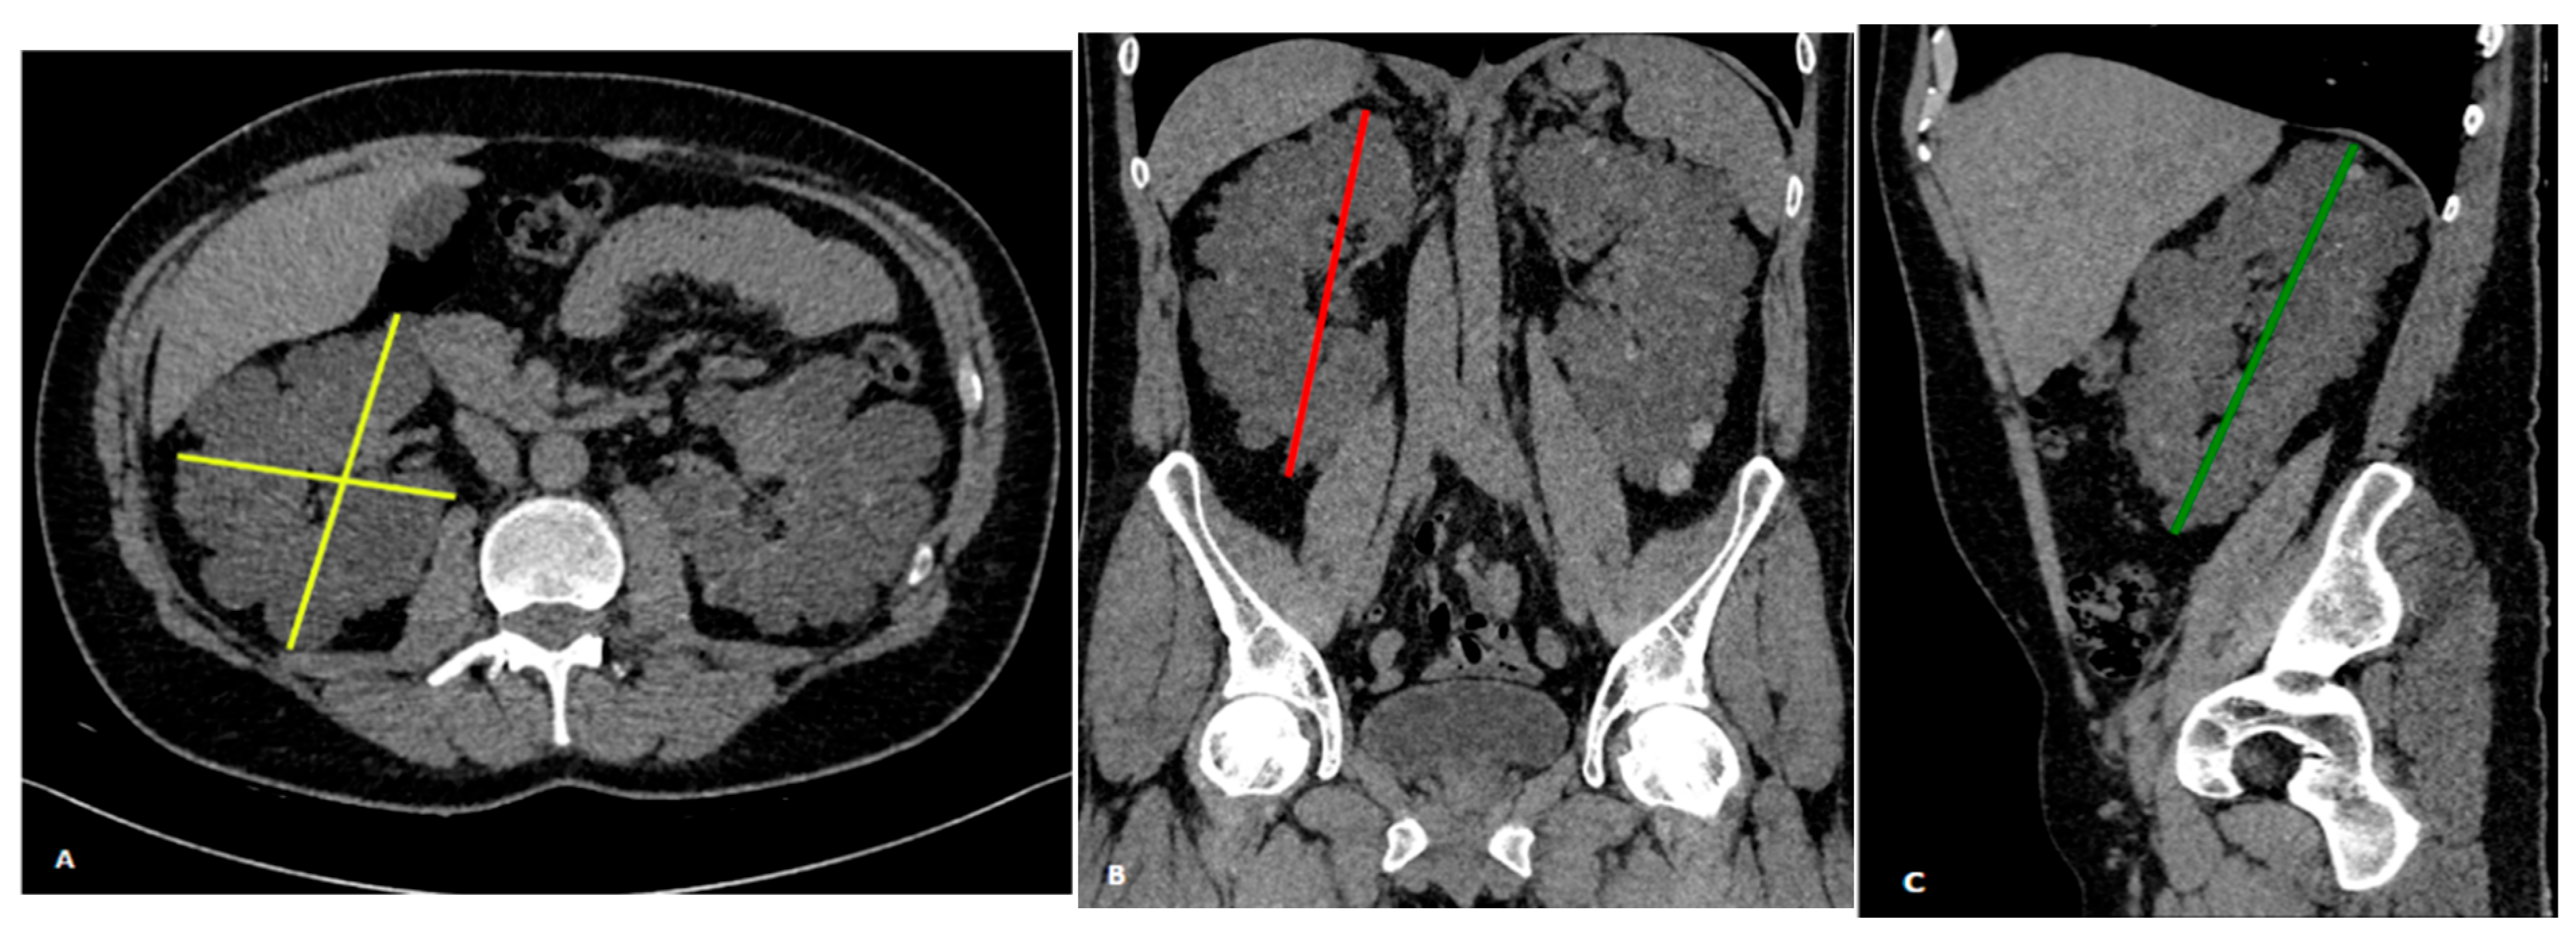

2.4. Ellipsoid Formula

2.5. Statical Analysis